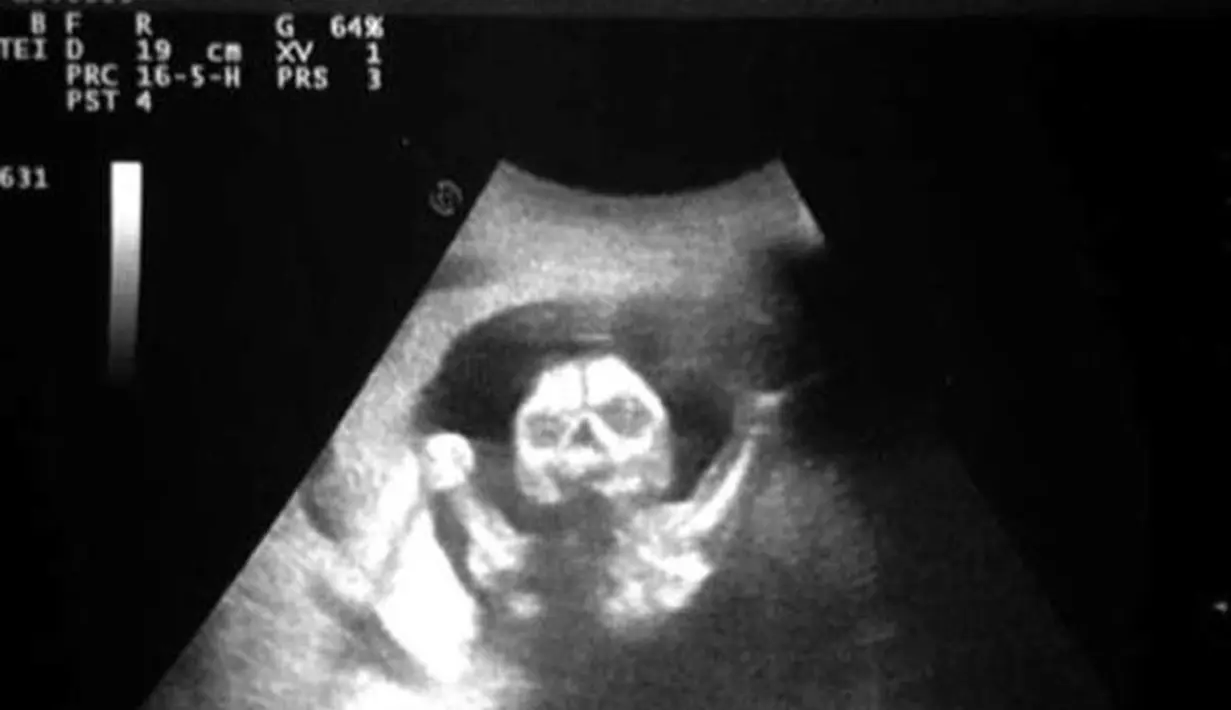

Ketika seorang ibu tengah mengandung, tidak jarang ia akan melakukan foto scan atau USG terhadap kandungannya. USG ini sendiri biasanya dilakukan untuk mengetahui jenis kelamin buah hati di dalam kandungan juga mengetahui tumbuh kembangnya.

Dan ketika melakukan USG kandungan, setiap ibu juga ayah janin berharap bahwa hasil USG begitu menggemaskan dan janin terlihat jelas. Sayangnya, tidak jarang hasil USG justru terlihat sangat menyeramkan, bikin merinding atau bahkan seperti ada sosok hantu di dalamnya. Seperti halnya hasil USG berikut ini.

Hasil USG ini memperlihatkan sesuatu yang menyeramkan dan bikin merinding karena seolah ada sosok hantu telah tertangkap kamera USG. Penasaran dengan foto-fotonya? Simak baik-baik galeri fotonya di bawah ini. Jika kamu tak berani melihatnya sendiri, usahakan untuk mengajak teman untuk melihatnya.